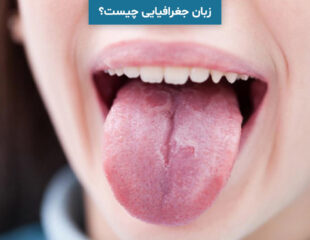

زبان جغرافیایی چیست؟ علائم، درمان و روش های تشخیص آن

زبان جغرافیایی یک بیماری خوش خیم دهانی بدون درد است که در آن لکه هایی در بالا و سایر قسمت ...